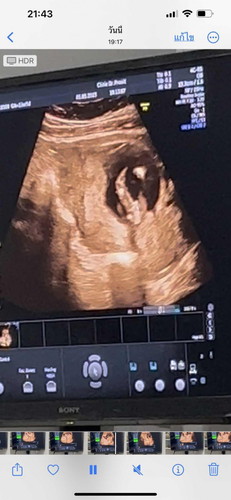

เมื่อวานไปฟังผลเลือดมา คุณหมอบอกว่าเราเสี่ยงสูง 1:169 ต้องส่งตัวเจาะน้ำคร่ำ พอได้ฟังรู้สึกใจสลาย เสียใจมากๆเลยค่ะ ร้องไห้จนไม่มีน้ำตาแล้ว มีแม่ๆคนไหนมีประสบการณ์แบบนี้มั้ยคะ โอกาศที่ผลเจาะน่ำคร่ำออกมาปกติ มีมั้ยคะ 😢😢😢 (เราอายุ24 แฟน31ค่ะ) #16w3d #ผลเลือดเสี่ยงสูง #ดาวน์ซินโดรม #ขอประสงการ์ณแม่ๆหน่อยคะ #ขอบคุณสำหรับคำตอบค่ะ